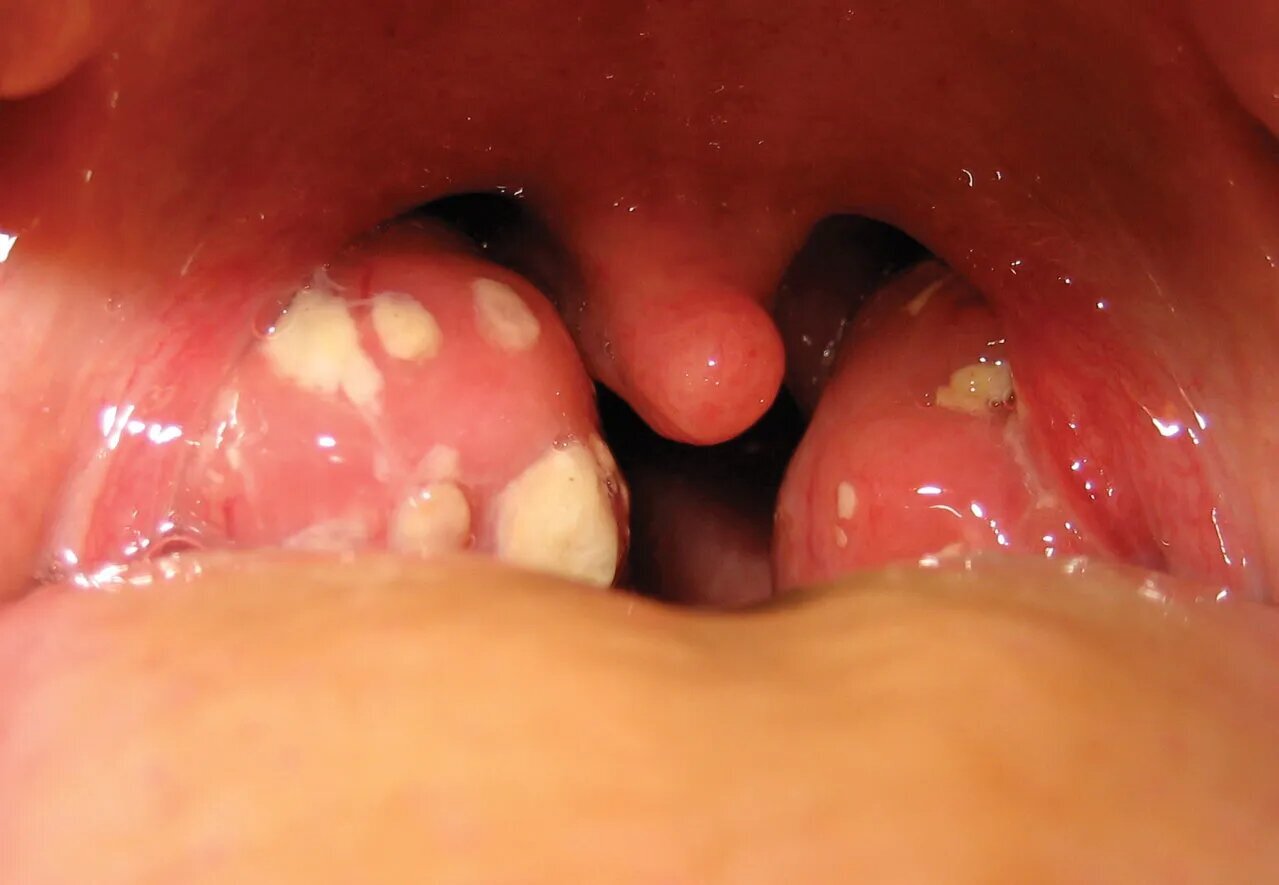

Ангіна не монолітна – вона поділяється на види, кожен з яких має свої особливості передачі. Катаральна ангіна, найлегша, нагадує простуду з почервонінням горла, але швидко поширюється через кашель. Фолікулярна форма йде глибше, утворюючи гнійні фолікули на мигдаликах, ніби маленькі вулкани, готові вивергнути інфекцію.

Найважча – лакунарна або гнійна ангіна, де гній заповнює заглибини мигдалин, перетворюючи горло на поле бою. Є ще вірусна ангіна, часто спричинена аденовірусами, яка передається як звичайна ГРВІ. Розуміння виду допомагає вчасно реагувати, бо бактеріальна ангіна, на відміну від вірусної, вимагає антибіотиків, щоб уникнути ускладнень на серце чи нирки.

Симптоми ангіни починаються гостро: біль у горлі, що ріже як ножем, супроводжується лихоманкою до 39-40°C і загальною слабкістю, ніби тіло перетворилося на ганчірку. Набряклі мигдалики з білим нальотом – класична картина, а лімфовузли під щелепою набухають, ніби сигнальні вогні небезпеки.